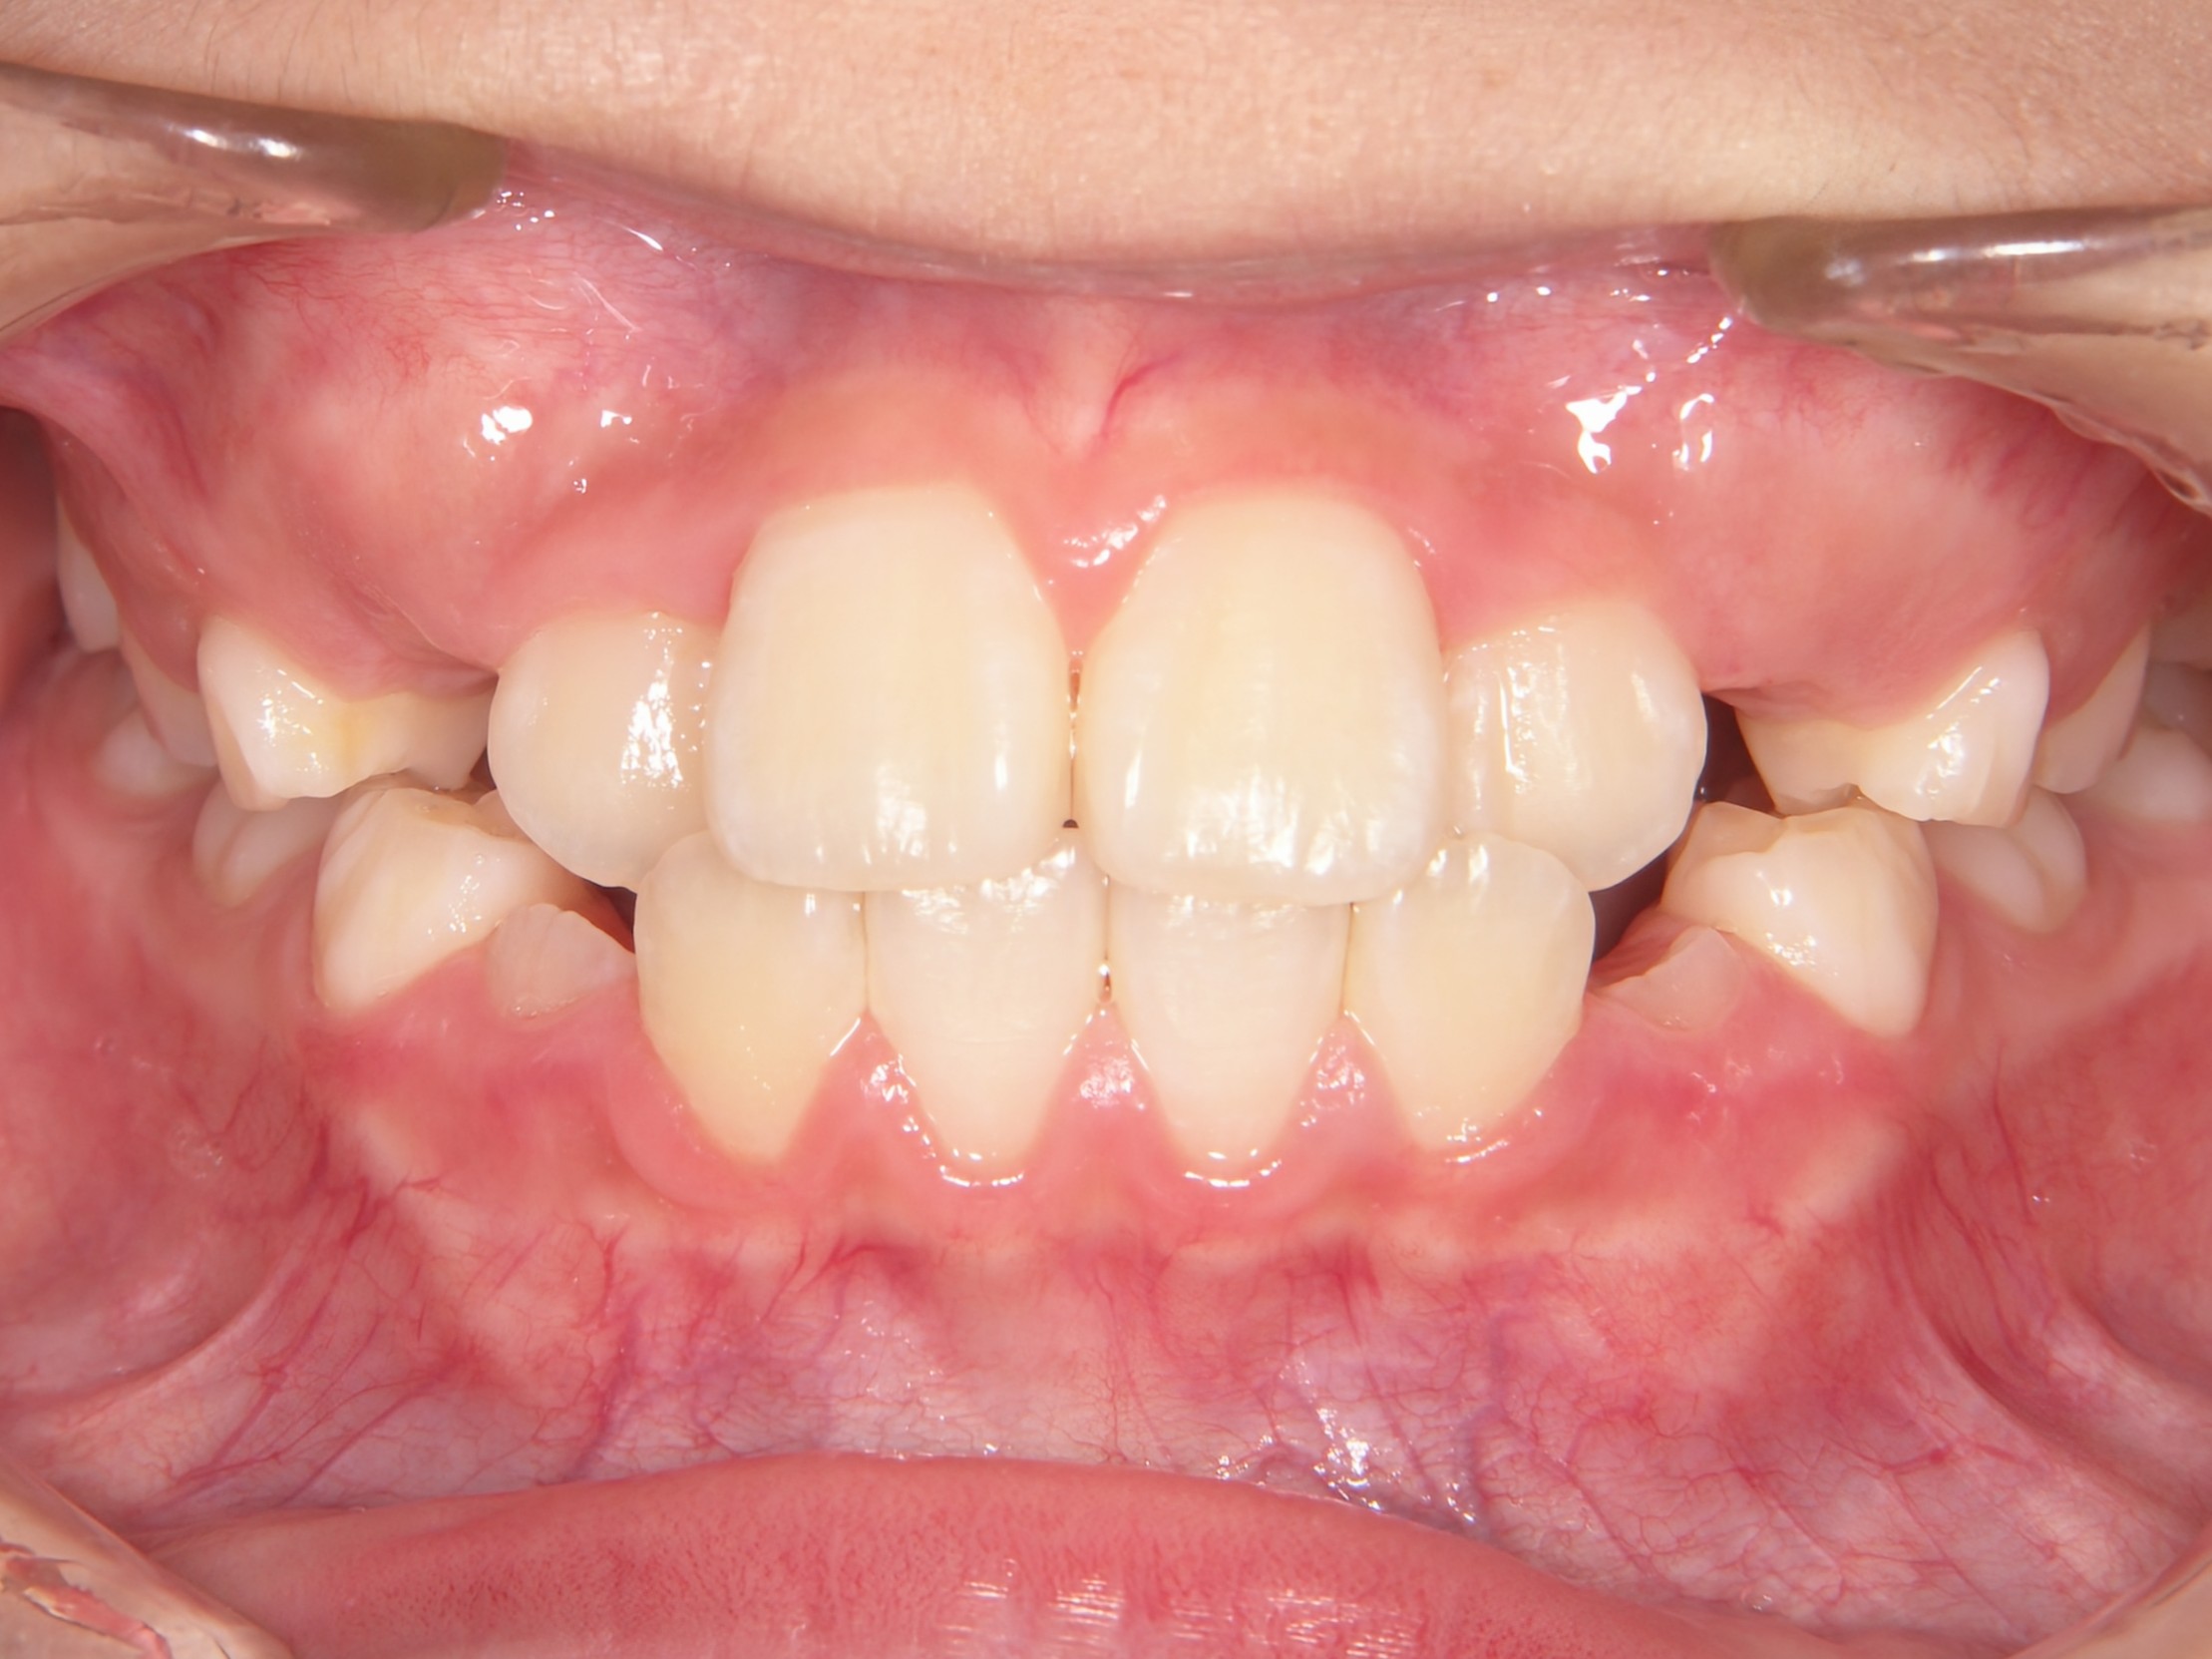

第2期治療開始時

顔貌写真

口腔内写真

開始年齢

13歳

主訴(患者様のお悩み)

残りの歯のデコボコを治したい

診断

上下顎軽度の叢生(上下の歯のデコボコ)

上顎右側犬歯低位(右上の八重歯)

治療方針

非抜歯矯正治療

全体的に装置を装着し、歯のデコボコや咬み合わせを治療

使用装置

表側矯正装置

治療期間の目安:約1年~1年半(保定期間を除いた期間)